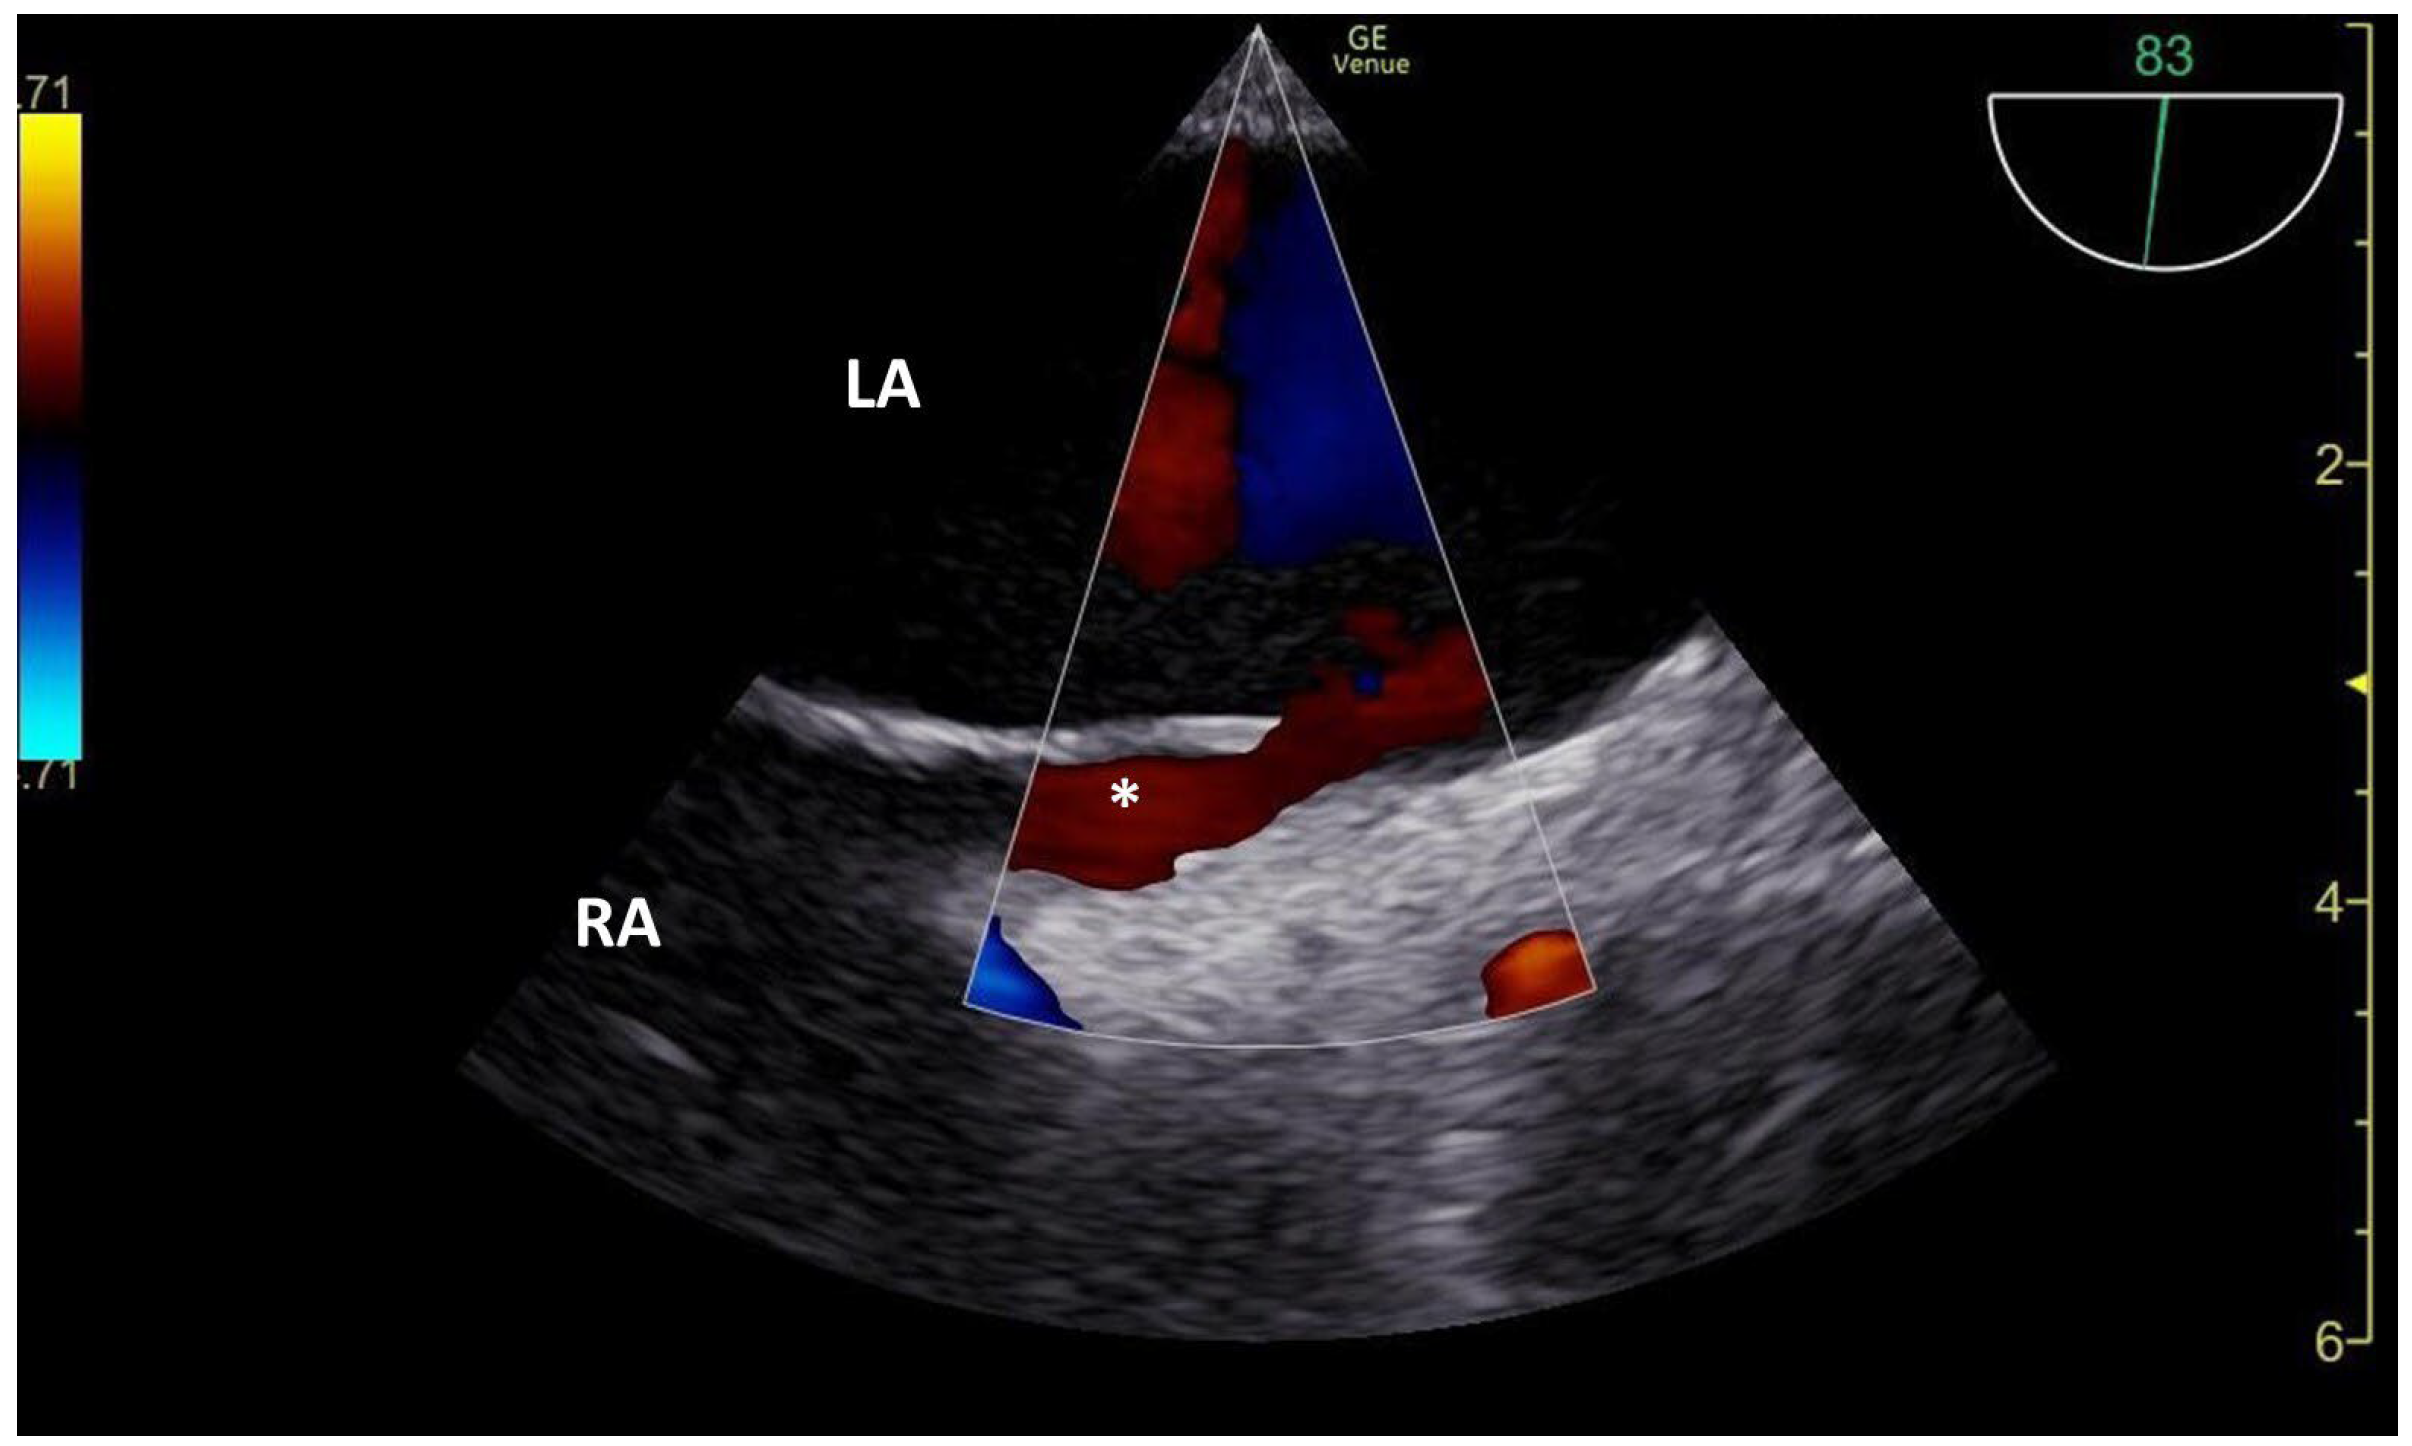

3.2. TCCD MES-Positive Case 2

| PFO | patent foramen ovale |

| TEE | transesophageal echocardiography |